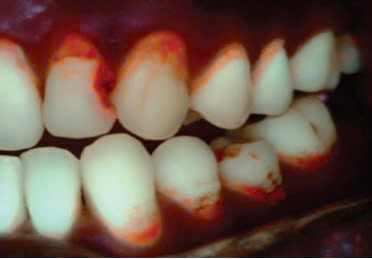

Ngoài ra, QLF có khả năng nhận diện mảng bám và cao răng.

QLF là công cụ đắc lực giúp phát hiện sớm tổn thương sâu răng ở: Sâu mặt nhai, sâu mặt bên, sâu răng bề mặt nhẵn, sau chân răng, sâu răng thứ phát và phát hiện mảng bám. Trong điều trị dự phòng, QLF cho phép đánh giá mức độ tái khoáng hay mất khoáng tiến triển của tổn thương sâu sớm chưa tạo lỗ, theo dõi sự phục hồi, dựa trên cơ sở độ giảm phát huỳnh quang có mối tương quan cao với mức độ mất khoáng trong mô răng. Đối với sâu mặt bên, việc chẩn đoán bị hạn chế hơn do sự đâm xuyên của ánh sáng bị cản trở, tổn thương được đánh giá gián tiếp thông qua ảnh chụp huỳnh quang ở mặt nhai.